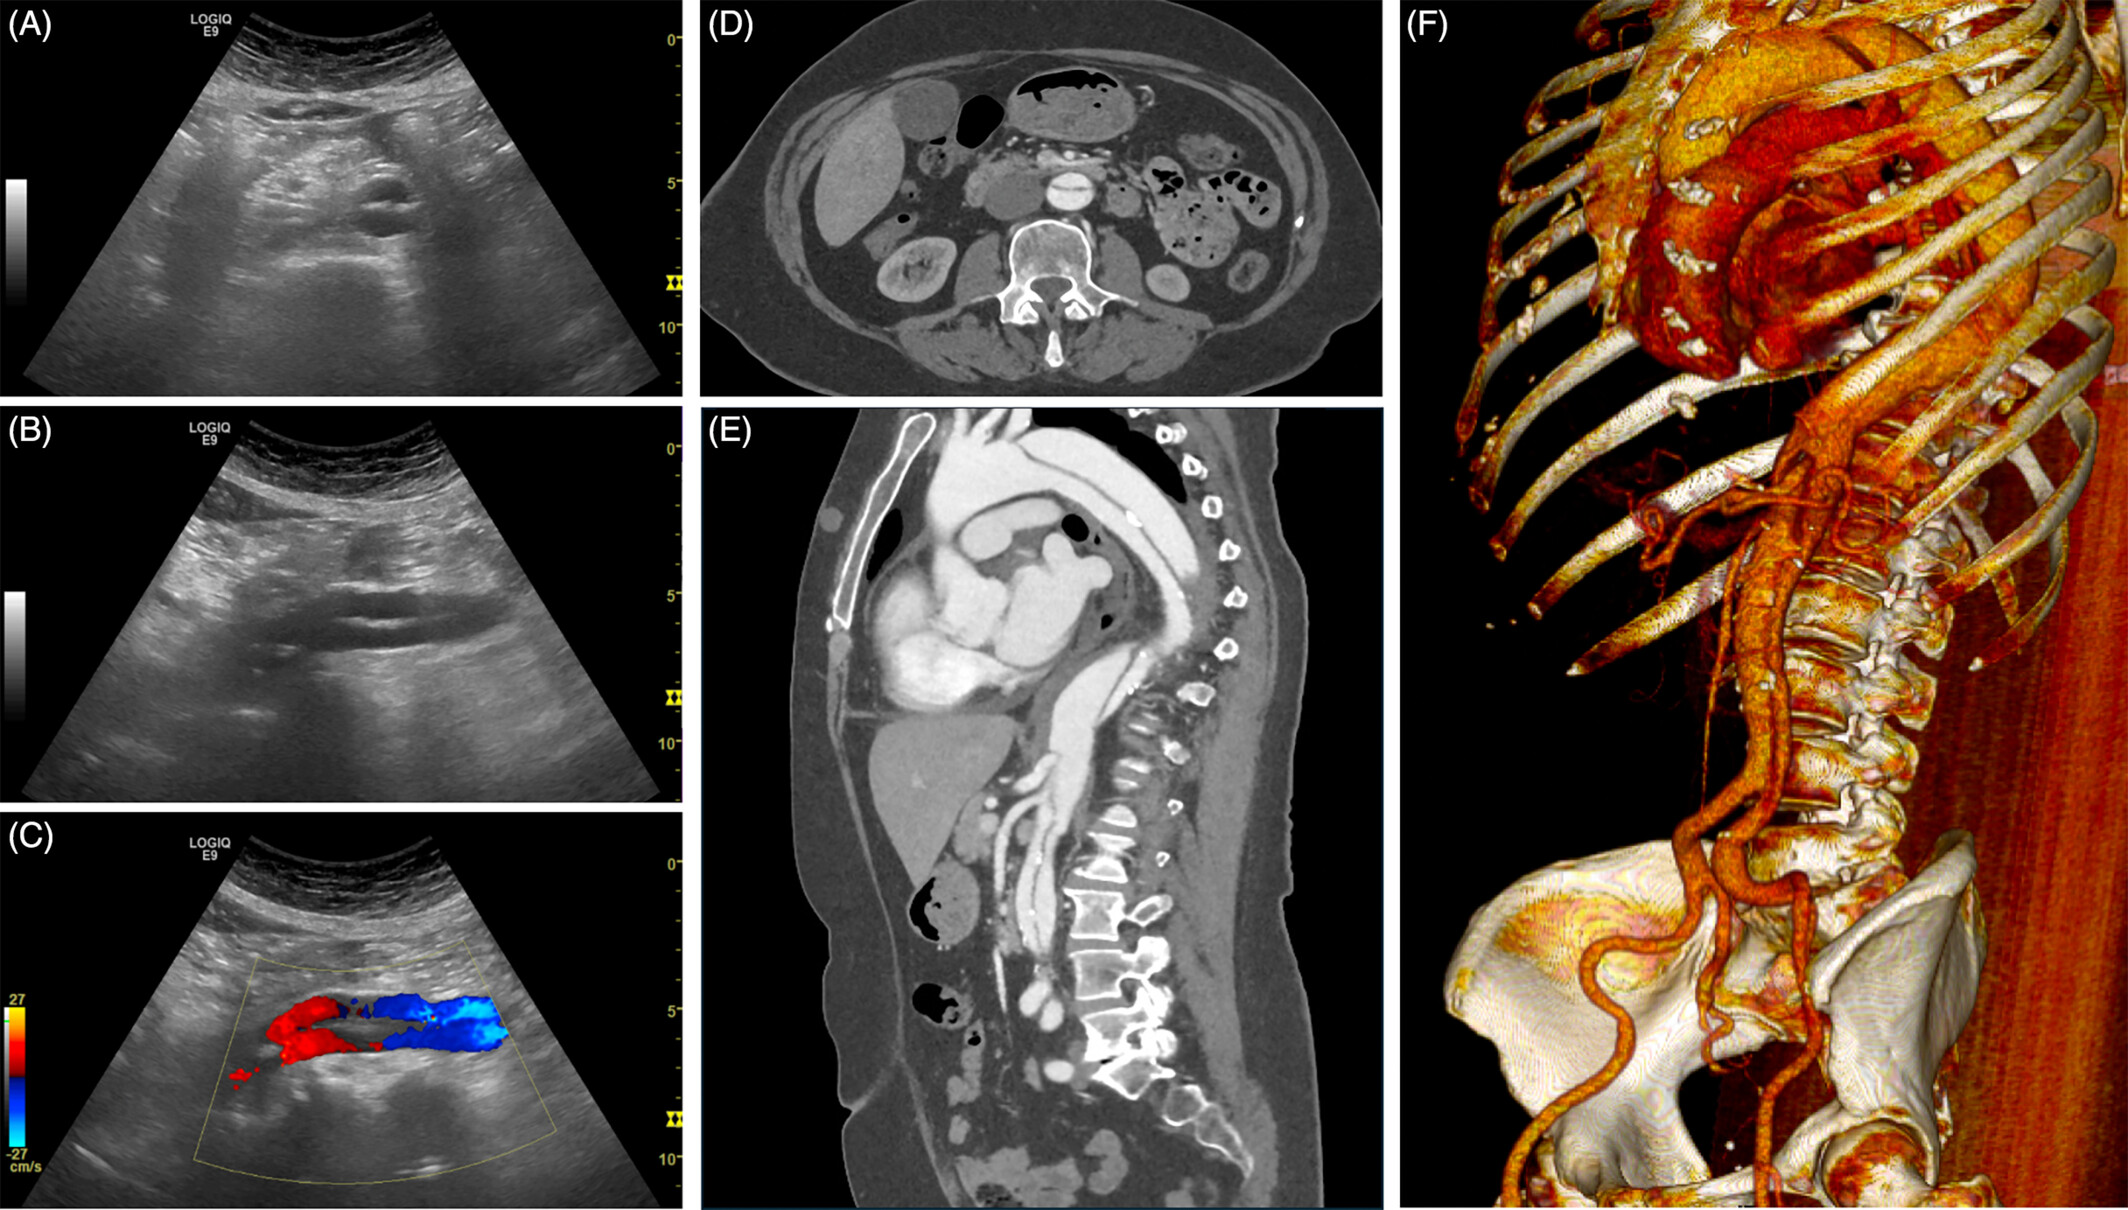

복부 대동맥 초음파 검사는 방사선 노출 없이 짧은 시간에 혈관 직경·벽 구조·혈류를 확인할 수 있어 응급상황을 예방하는 1차 선별검사로 각광받고 있습니다.

복부 대동맥류(AAA)

- 직경 3 cm 이상, 또는 정상 대비 50% 이상 확장된 상태를 말합니다.

- 5.5 cm 이상이면 파열 위험이 급격히 증가하므로 수술·스텐트 삽입을 검토합니다.